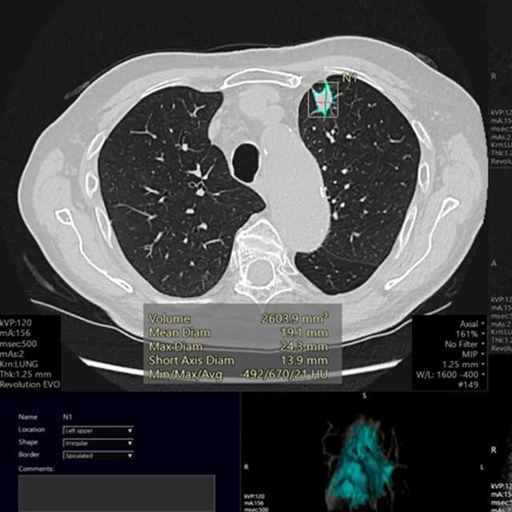

故而现在强调早诊断早治疗,尤其是高危人群需要定期接受体检。常规检查如胸部平片、CT等都可以在一定程度上排除肺癌的风险。CT年度筛查能发现85%的I期周围型肺癌,术后10年预期生存率超过90%。

研究显示,目前的AI医生在诊断早期肺癌的准确率、敏感性等方面已经超越了人类医生(作者注)▼